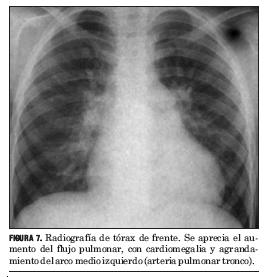

2. RADIOGRAFÍA DE TÓRAX (FIGURAS 7 Y 8)

- Cardiomegalia.

- Dilatación de aurícula y ventrículo derechos (aumento del contacto esternal en el perfil).

- Dilatación del tronco de la arteria pulmonar y sus ramas con aumento de la circulación pulmonar.

- En caso de enfermedad vascular pulmonar (síndrome de Eisenmenger) se observará dilatación del árbol arterial pulmonar central con hipovascularización periférica (imagen del “árbol de invierno”) y disminución del tamaño cardíaco.